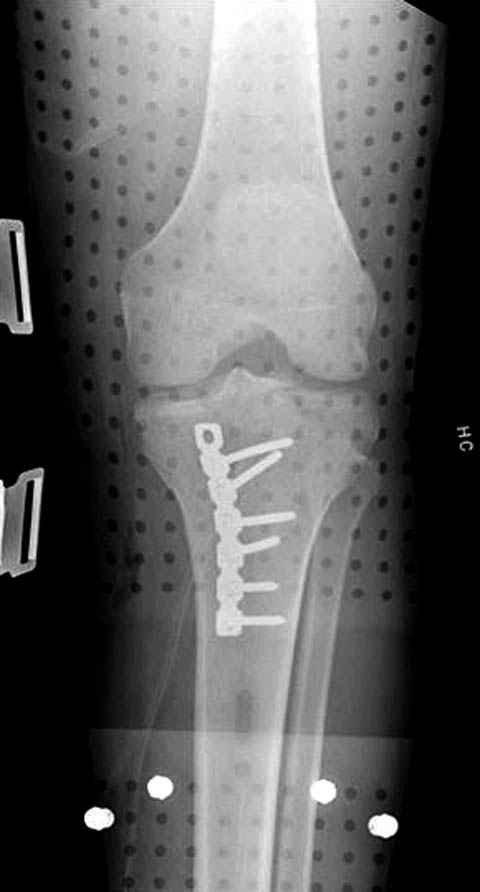

Трудно поверить, что разрекламированная Ортопедическая школа Восточной Украины позволяет такие странные снимки? На прямом снимке сохранен общий контур плато, но не известна судьба импрессии суставной поверхности. На полубоковой?, оставлен без репозиции задне-медиальный отдел, и навряд ли после такой фиксации можно удовлетвориться результатом.

Такая ситуация характерна для многих, когда принимается ошибочное решение, т.е пытаются фиксировать одним имплантом переломы двух мыщелков. Латеральная пластина приемлема только для тех случаев, когда сохраняется интактным медиальный диафизарный кортекс и отсутствует фрагментация на верхушке медиального перелома.

При сложных переломах тибиал плато для своего рода Damage Control мы иногда применяем поэтапную тактику. Сперва оперируется одна сторона, а потом после рекондиции мягких тканей окончательный этап.

Если состояние мягких тканей позволяет, я бы предложил такой метод для вашего больного. Без предварительного планирования будет трудно, но шанс не надо упускать. Всего несколько дней после операции, и такая тактика лучше, чем недовольный молодой пациент.